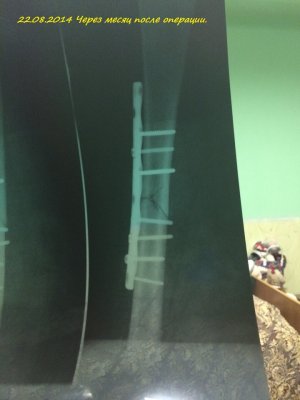

Здравствуйте! Мне 19 лет. 16.07.2014 года у меня случился закрытый перелом с/3 правого бедра со смещением. Произошло это так: я решила заниматься бегом. Каждый день бегала по стадиону минут 30-40. Получилось так, что я бежала, потом споткнувшись правой ногой, вернее как только я споткнулась, услышала хруст и упала на левую сторону. Сначала вообще не поняла, что произошло. Попыталась пошевелить ступней, особых болевых ощущений не испытала и решила попробовать встать, как только я попыталась поднять ногу, я увидела как у меня в бедре "шевелятся" кости. В итоге вызвали скорую, сделали рентген (все снимки я загрузила), поставили спицу под б/берцовую кость, почти под коленом, и я лежала 6 дней на вытяжке. 22.07.2014 года был проведен Экстрамедуллярный остеосинтез правого бедра пластиной АО (все пишу из выписки медицинской карты)Причем, прошу заметить на снимках может быть не видно, во время операции обломалось сверло, и пластину не закрепили по краям, я, конечно, мало что понимаю. 4.08.2014 года мне наложили гипс и отправили домой. 15.09.2014 года сняли гипс, я стала постепенно разрабатывать ногу, ходить, примерно 1.10.2014 года я стала ходить с тростью, все вроде бы шло на поправку. 23.10.2014 года меня выписали, и я уехала учиться в ВУЗ. Примерно вначале декабря я упала с лестницы(примерно со 2-ой ступеньки, при этом все это время я ходила с тростью). Стала болеть нога, я пошла в больницу, вновь снимок. Сказали все нормально-срастается. Назначили магнит(10 дней), отходила я на магнит. Все стало нормально, после НГ я могла ходить без трости, немного хромала, носила ее с собой, и когда уставала-ходила с ней. Вначале марта, примерно с 5-ого числа, стали мучить очень сильные боли, причем болело колено, очень тянуло берцовые кости, иногда беспокоило место перелома, вновь иду в больницу, опять снимок. И УЖАС! На снимке видно, как у меня кривится кость, чуть ли не ломаясь пополам, и переломана пластина. Мне говорят, что нужно делать операцию, врач сказал, что пластину не будут ставить повторно, эту уберут, все почистят и поставят штифт.